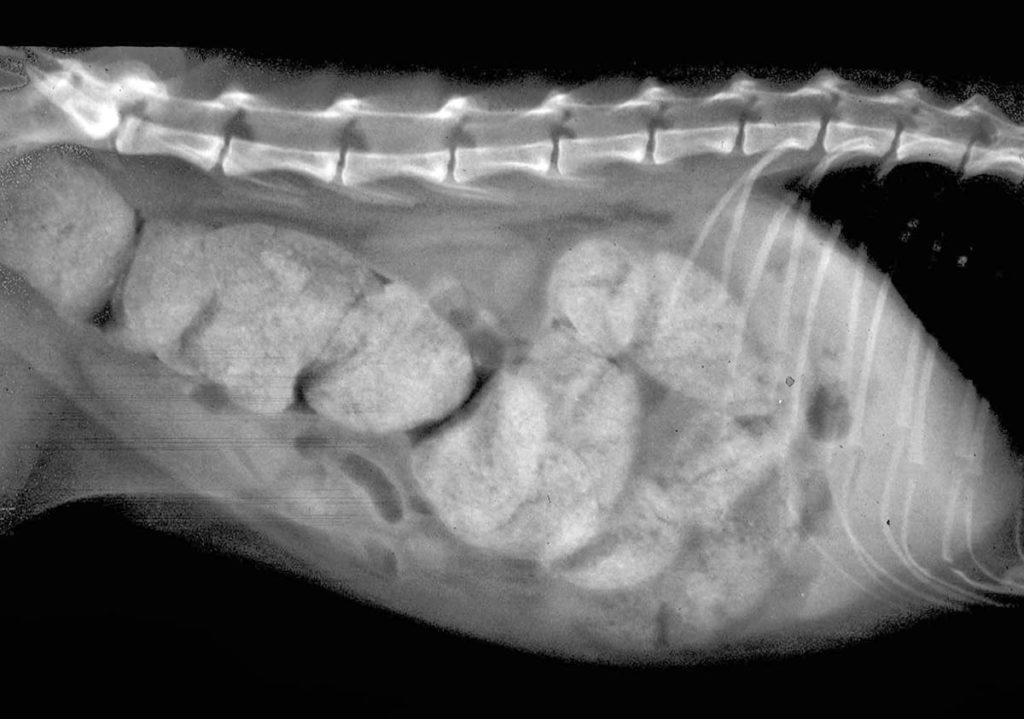

При обнаружении в лотке следов крови или слизи слабительные средства давать запрещено. Животное нужно отвести к ветеринару для проведения диагностического обследования. При серьезной непроходимости кишечника питомцу может потребоваться оперативное вмешательство.

Причины запора, как понять

Задержка нормального отправления естественных потребностей с возрастом усугубляется. У возрастного питомца (пожилой кошки) тормозится протекание всех процессов в организме. Перистальтика кишечника ослабляется и возникают проблемы с выведением кала из тела животного. Статистика показывает, что самцы семейства кошачьих страдают снижением проходимости кишечного тракта гораздо чаще, чем представительницы слабой половины.

В качестве наиболее часто встречающихся причин запора ветеринары называют:

- неправильную диету (объедки со стола, отсутствие в пище клетчатки);

- посторонний предмет в кишечнике (проглоченный инородный объект);

- шерстяной комок у британского, шотландского кота, мейн куна;

- пониженная физическая активность питомца;

- воспалительные процессы в толстом кишечнике;

- заражение гельминтами;

- опухоли кишечного тракта (доброкачественные или злокачественные);

- порок развития толстой кишки (мегаколон);

- заболевания внутренних органов, приводящие к торможению процессов переваривания пищи;

- побочный эффект процедуры стерилизации, у кастрированных котов;

- стресс, проблемы с нервной системой;

- болезнь простаты у самца;

- последствия травмы.